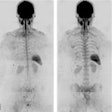

Whole-body DWI-MRI could aid treatment of myeloma